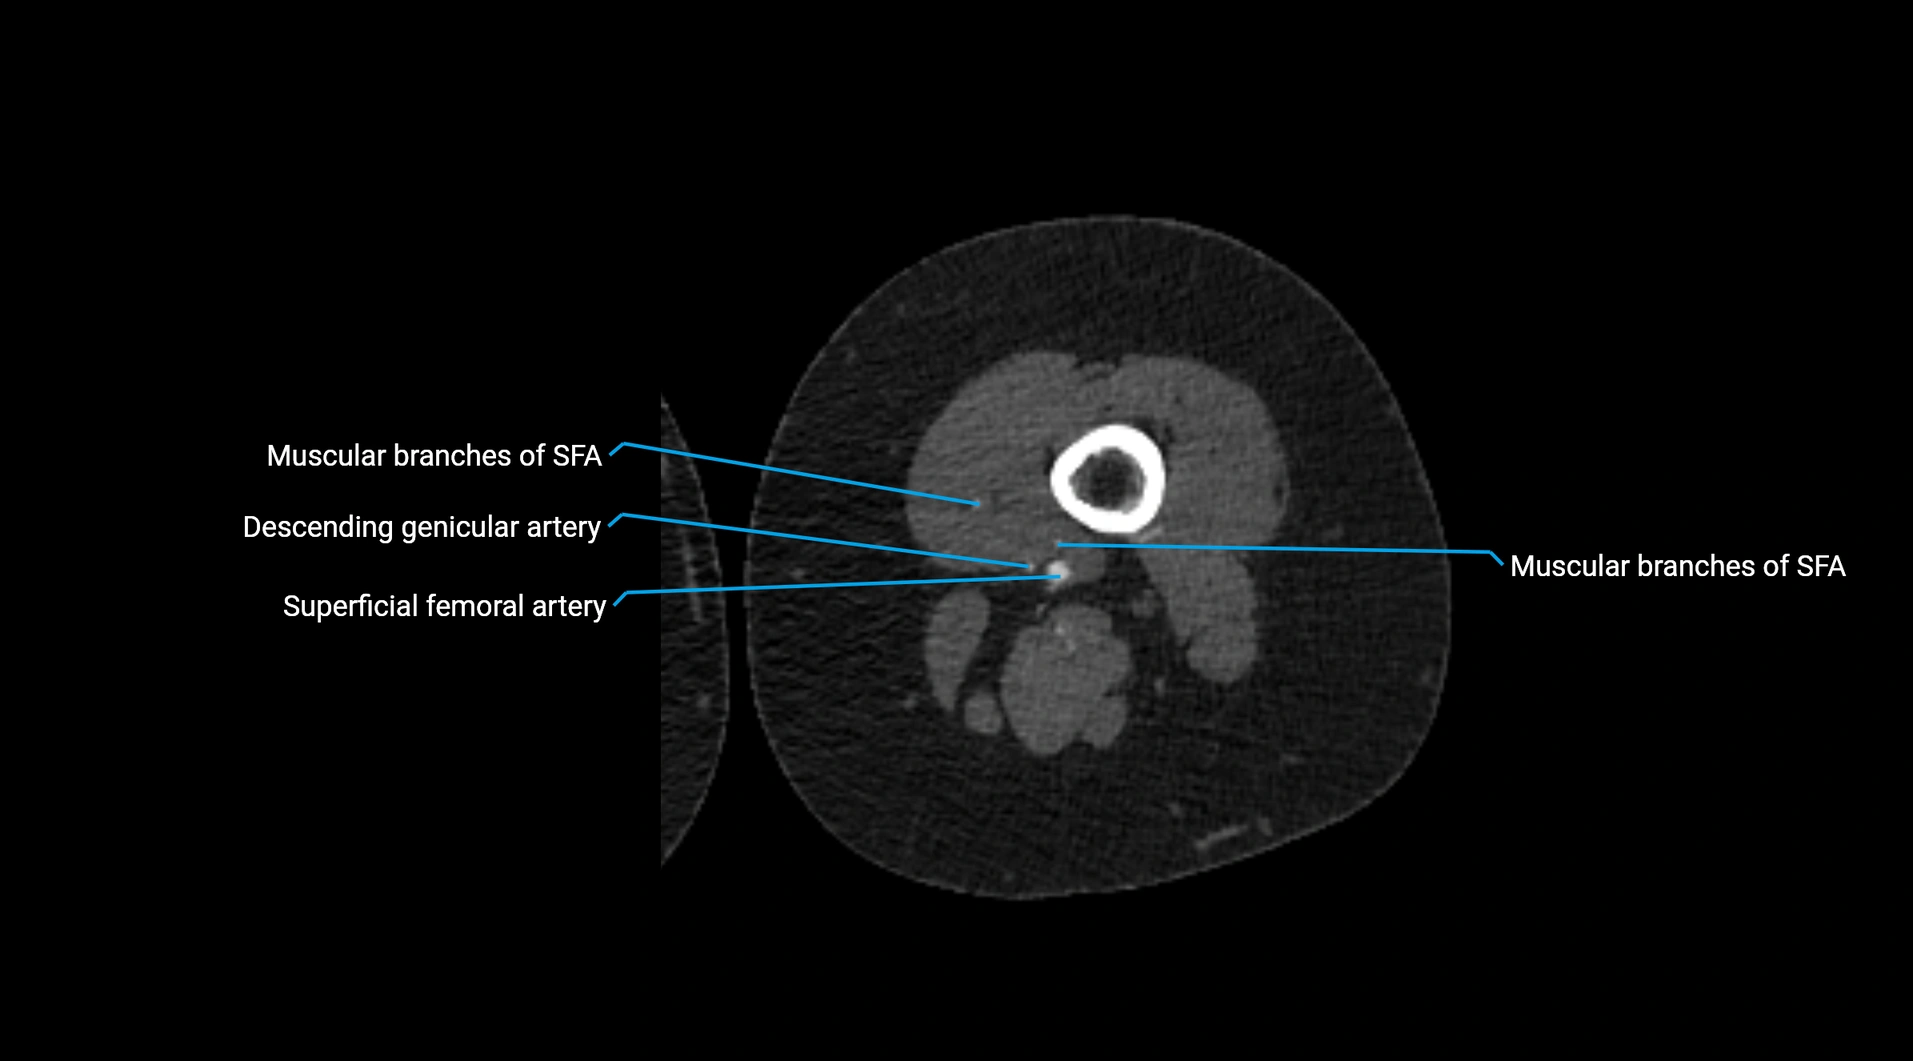

CT images

image